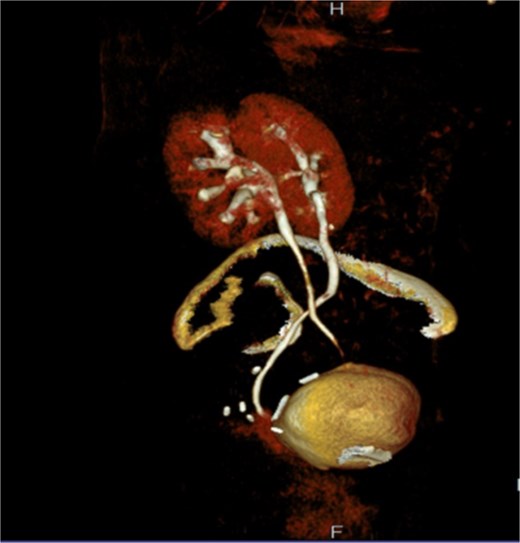

Two months later, the symptoms gradually reoccurred and a retrograde cystography and CT cystography were performed demonstrating the known UVF and as a new finding the formation of a VVF (Fig. 2). Based on these findings, a surgical repair with an open abdominal exploration was decided.

A: Retrograde cystography with contrast enhancement showing the existence of a VVF. B and C: CT cystography showing passage of contrast enhancement from the bladder to vagina, demonstrating the formation of a VVF.